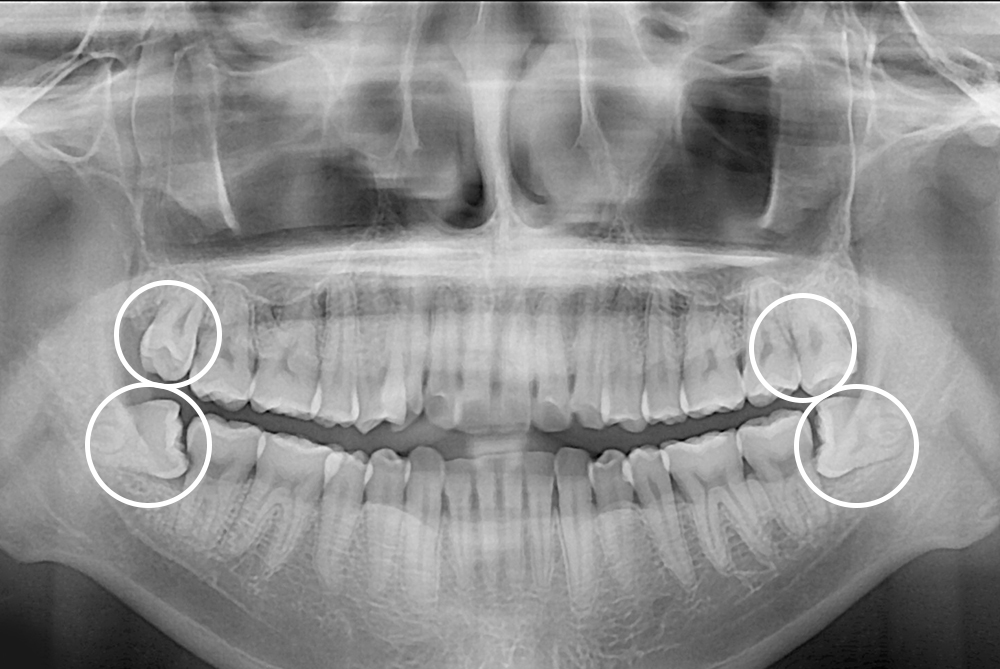

[사랑니] 매복 사랑니 발치

치료후 : 2023-12-02

세종치과는 구강악안면외과학 박사이신 원장님이 발치하는 치과입니다.